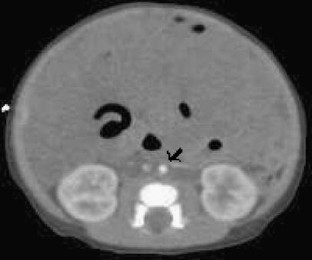

Enhanced CT perfusion cut-off sign in midgut volvulus

We present a case of malrotation with midgut volvulus in an infant in which we discovered a unique CT sign called the perfusion cut-off sign. We hope this case will help establish this crucial diagnosis in other cases.

Fig. 3